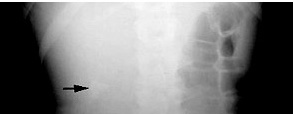

Presented with renal stone and hypercalcemia